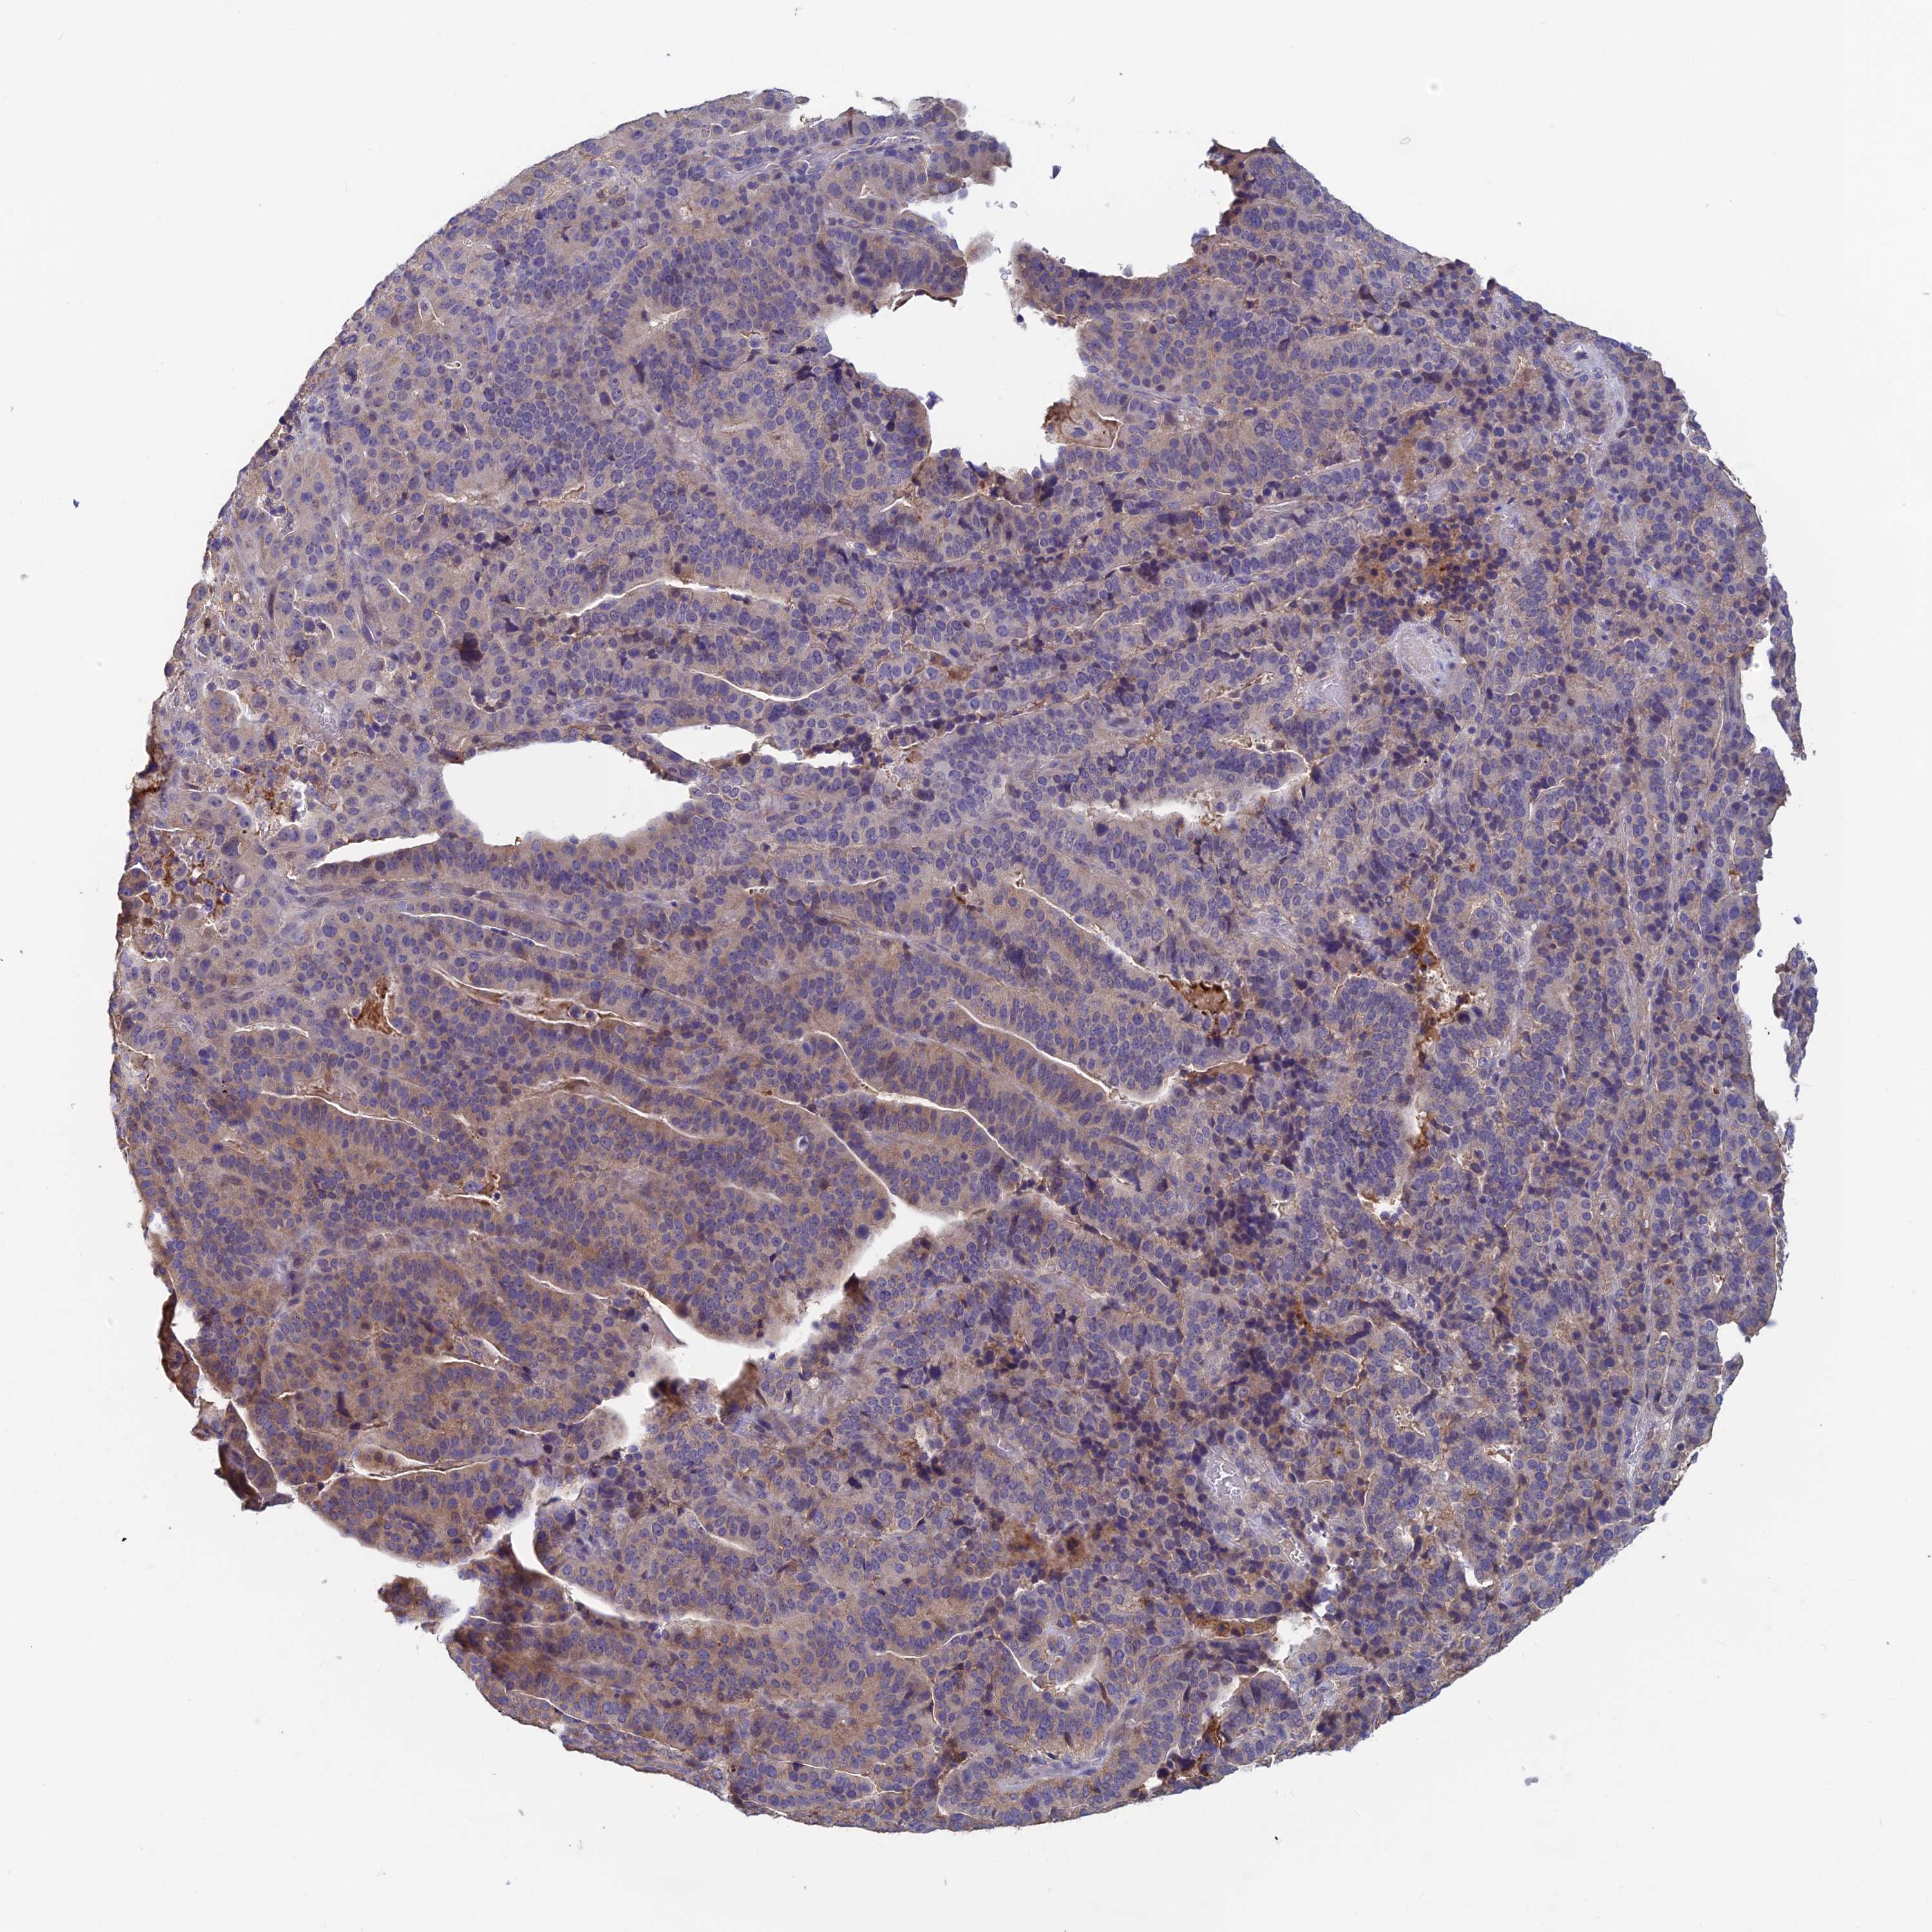

STOMACH CANCER - Protein expressioni

A mouse-over function shows sample information and annotation data. Click on an image to view it in a full screen mode. Samples can be filtered based on level of antibody staining by selecting one or several of the following categories: high, medium, low and not detected. The assay and annotation is described here.

Antibody stainingi

Antibody staining in the annotated cell types in the current human tissue is reported as not detected, low, medium, or high, based on conventional immunohistochemistry profiling in selected tissues. This score is based on the combination of the staining intensity and fraction of stained cells.

Each image is clickable and will lead to virtual microscopy that enables deeper exploration of all samples and also displays staining intensity scores, fraction scores and subcellular localization as well as patient and tissue information for each sample.

Antibody HPA042313

Staining

High

Medium

Low

Not detected

Intensity

Strong

Moderate

Weak

Negative

Quantity

>75%

75%-25%

<25%

None

Location

Nuclear

Cytoplasmic/membranous

Cytoplasmic/membranous,nuclear

Adenocarcinoma, NOS